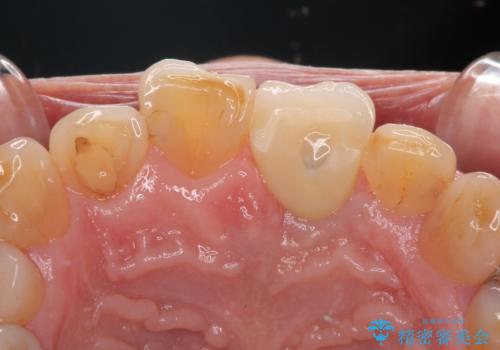

歯肉形態を概ね回復するタイミングでインプラントを埋入し、補綴治療を行うこととしました。

歯肉移植術による更なる歯肉ラインの改善も検討しましたが、笑ったときに歯肉ラインは唇に隠れてしまうため、現在の位置にて仕上げることとしました。

骨の前後幅が小さかったため、細いインプラントを選択せざるを得ない状況でした。咬合力が非常に強い方のため、就寝時のマウスピース装着を徹底していただき、インプラントへの負担を軽減することとしています。